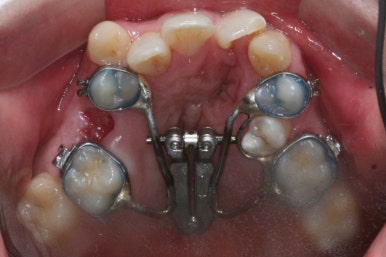

악궁확장이 시작될 시점과 악궁확장을 다 진행했을 시점의 비교입니다.

확실히 좁아져 있던 가로 넓이가 넓어진 것을 볼 수 있습니다.

악궁확장장치는 바로 제거할 경우 다시 원상태로 폭이 좁아질 수 있으므로 3~6개월은 유지해야 합니다.

만약 치아교정 없이 악궁확장장치만 사용한다면 유지장치가 매우 중요하게 됩니다.